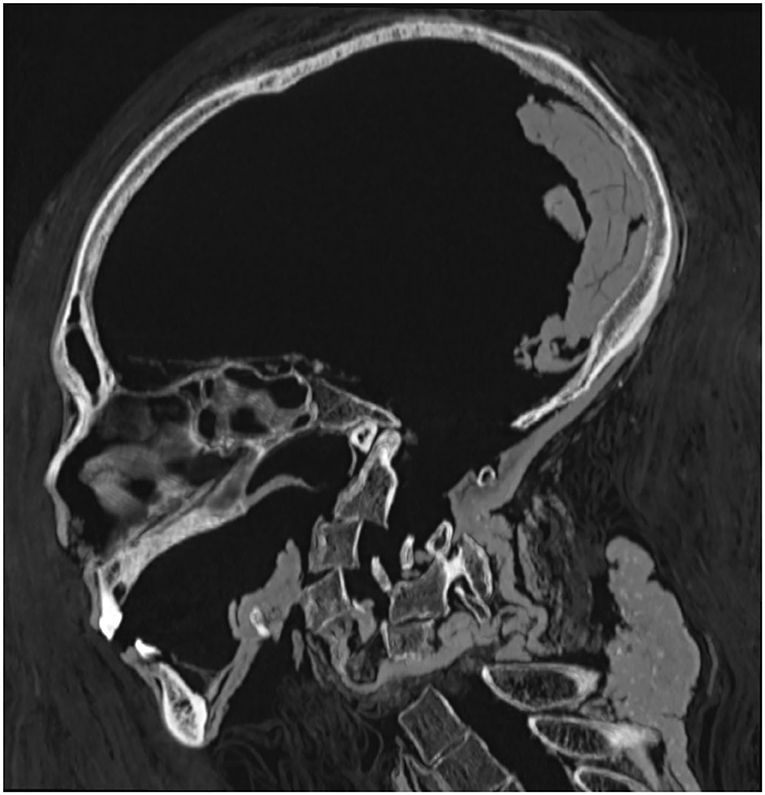

Mas, graças à tecnologia de tomografia computadorizada (TC), os pesquisadores da Universidade do Cairo recentemente “desembrulharam” Amenhotep digitalmente para aprender sobre sua vida e dinastia.

Esse dano foi “reparado com amor” pelos padres mortuários da 21ª Dinastia, cerca de 400 anos após a morte de Amenhotep. Eles usaram uma faixa de linho tratada com resina para recolocar a cabeça e o pescoço juntos.

A primeira vez que os arqueólogos usaram uma tomografia computadorizada para examinar uma múmia foi em 1977.